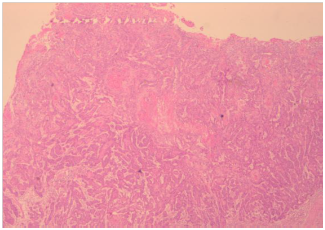

The patient was then planned for a partial penectomy along with transurethral resection of the bladder tumour. The patient underwent a partial penectomy (Figure 3) along with transurethral resection of the bladder tumour. The pathology results from the TURBT (Transurethral resection of bladder tumour) revealed a low grade transitional cell carcinoma, with no muscle invasion (Figures 4 & 5). Penile resection specimen showed a moderately differentiated squamous cell carcinoma with no lympho vascular invasion with the re-sected margin being negative for tumour (Figures 6 & 7). The TNM stage of the penile and bladder tumour was T1N0M0 and T1N0M0, respectively. The final diagnosis was double primary cancer of the penis and bladder. The follow-up check Cystoscopy and CT scan of the abdomen and pelvis done six months after the operation showed no evidence of recurrence. The inguinal lymphadenopathy too subsided post-operative lyon antibiotics treatment, presumably being reactive in origin. Patient reports no lower urinary tract symptoms and has good stream and minimal post void volume.8

Figure 6 Low power magnification of bladder tumor.

Figure 7 High power magnification of bladder.